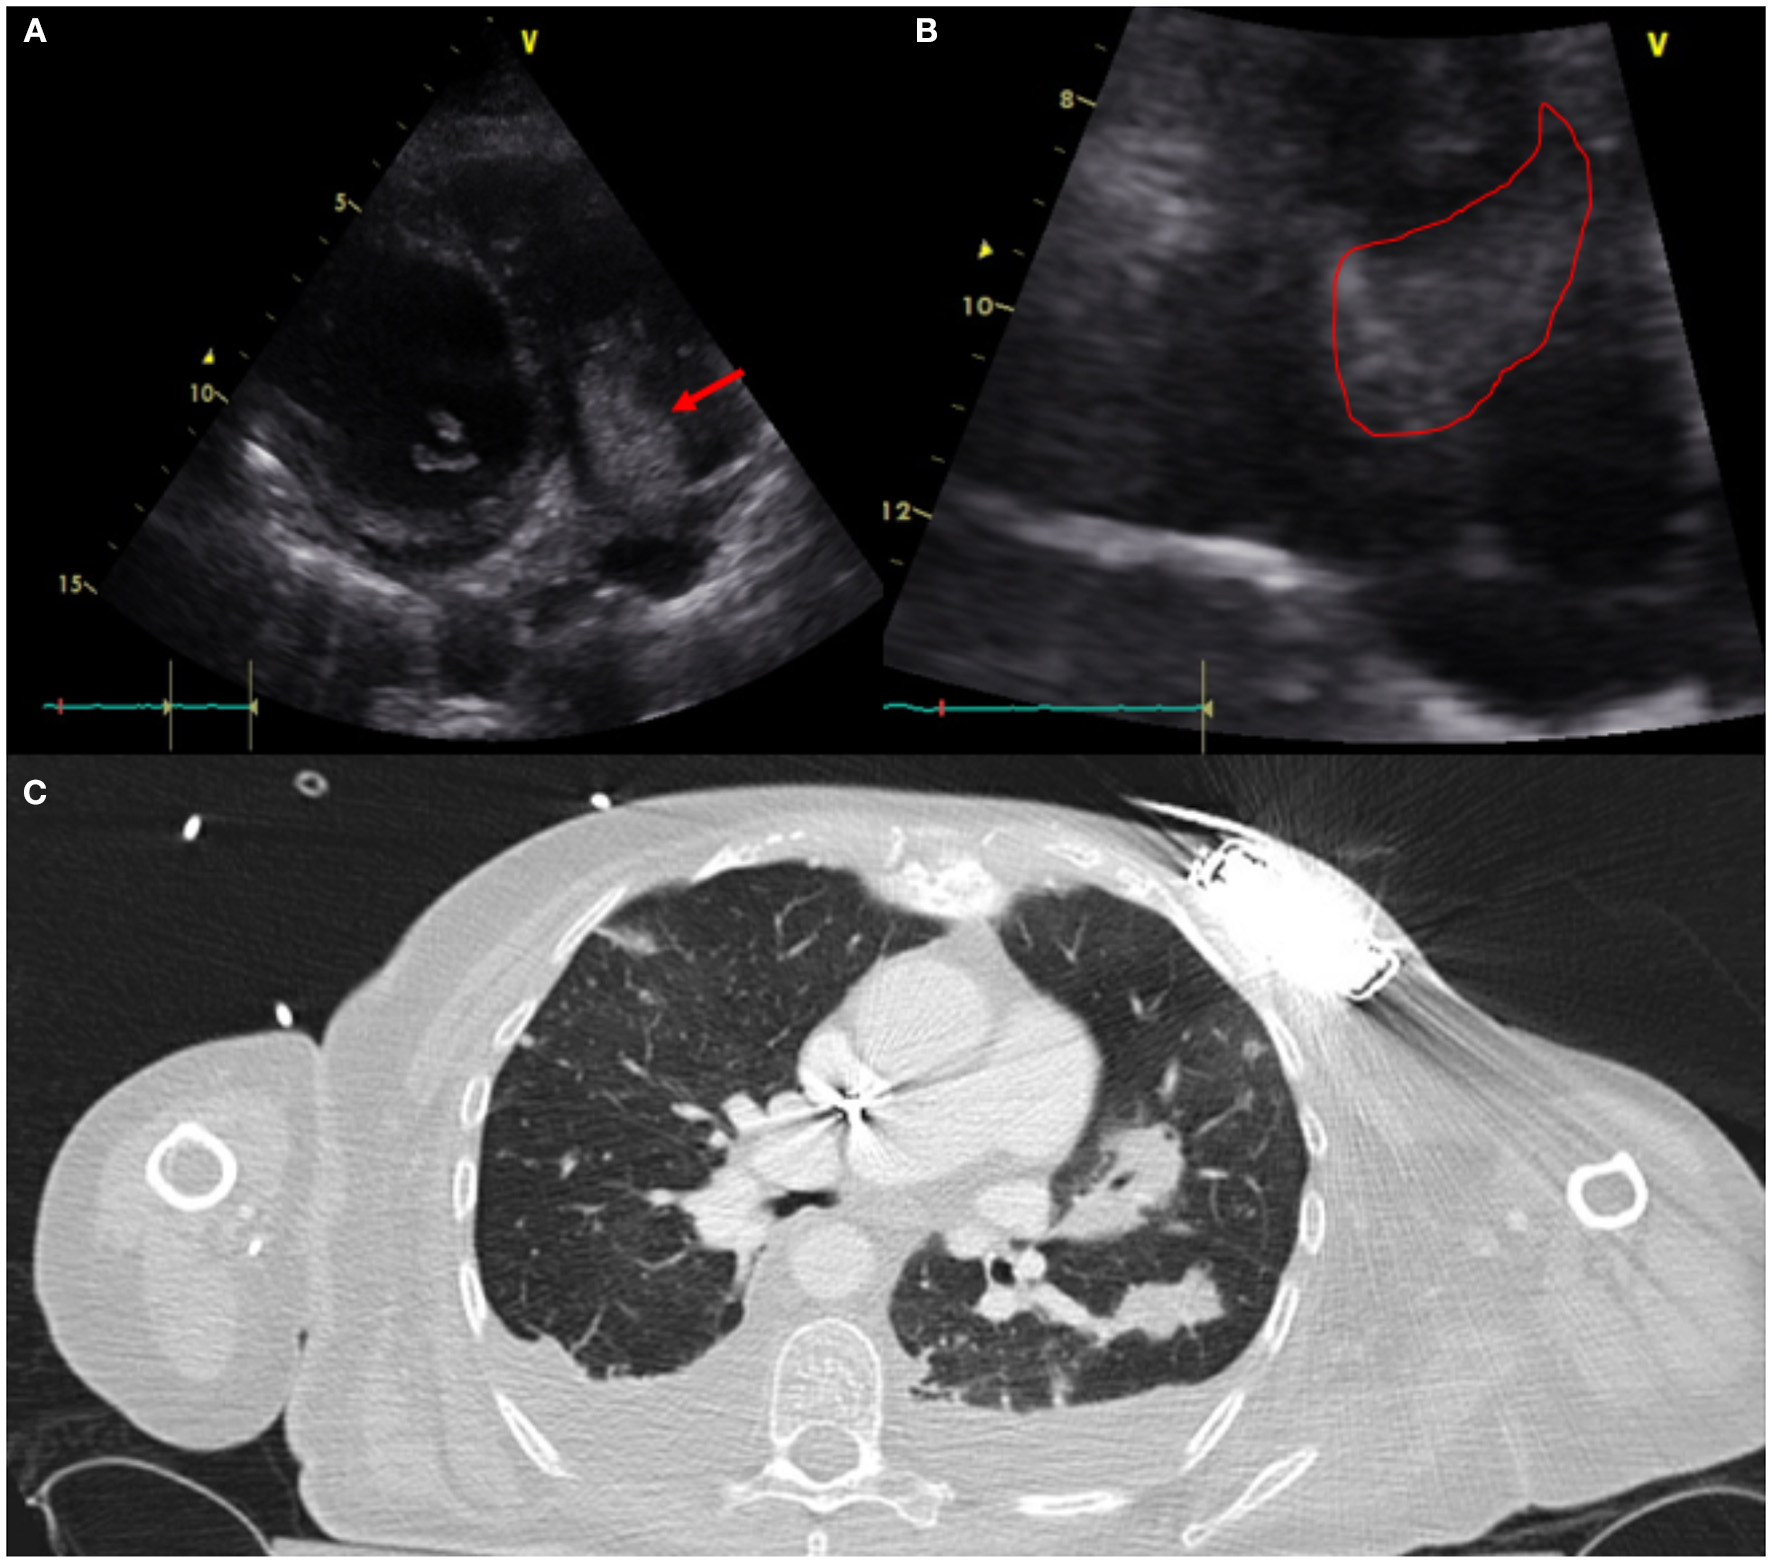

CIED-IE most commonly affects the tricuspid valve (3, 16). This is particular important to diagnose because of its management implications that might require open heart surgery for system extraction and valvular intervention in some situations (i.e large >2cm vegetation and/or pulmonary embolism) versus percutaneoussystem extraction (5). In cases requiring system extraction only, the use of CT for pre-procedural planning has become a great asset to define adherence of leads to surrounding vasculature which would require more specialized equipment and more experienced operators for successful system extraction (17) (Figure 3).

Figure 3

Sixty one year-old woman with a history of NICM s/p single lead ICD who presented with fever and malaise. Infectious work up was positive for MSSA bacteremia. TTE showed a very large vegetation attached to the ICD lead in the RA protruding into the RV [(A)-modified apical view and (B)-RV focused view with RA zoom]. A pre-procedural CT (C) was obtained and revealed bilateral, extensive and multifocal septic emboli with cavitary lesions as well as bilateral pleural effusions without evidence of pocket infection. The patient underwent open sternotomy with device extraction and TV repair for septal leaflet perforation for management of CIED systemic infection with IE.